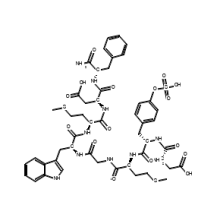

Our expertise in biological and chemical systems

Our products

Discover our products